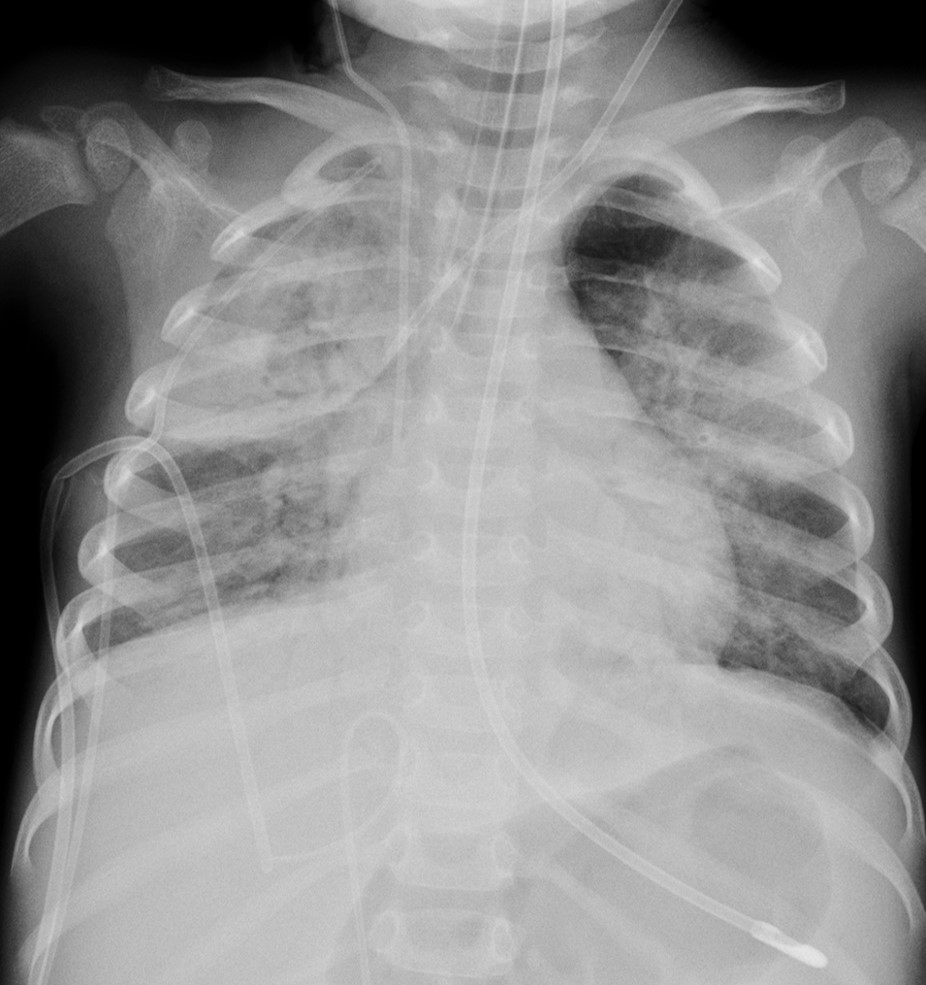

¿Cuál de estas afirmaciones es correcta en la siguiente radiografía de tórax?

El paciente presenta extensas consolidaciones parenquimatosas pulmonares con broncograma aéreo. El extremo del tubo endotraqueal se localiza excesivamente bajo, quedando dirigido hacia el bronquio principal izquierdo. Existe un catéter venoso femoral (solo visualizamos la porción distal) que queda mal posicionado haciendo un bucle en la VCI.

No es correcta. El paciente tiene consolidaciones pulmonares bilaterales, con el tubo endotraqueal y un catéter venoso femoral mal posicionados.

No es correcta. El paciente no presenta signos de pérdida de volumen que sugieran atelectasias.

No es correcta. La imagen de la radiografía de tórax está bien centrada, colimada, penetrada e inspirada, y no está movida. Técnicamente no presenta alteraciones.

"El extremo del tubo endotraqueal se localiza excesivamente bajo, quedando dirigido hacia el bronquio principal izquierdo", ¿no sería derecho?